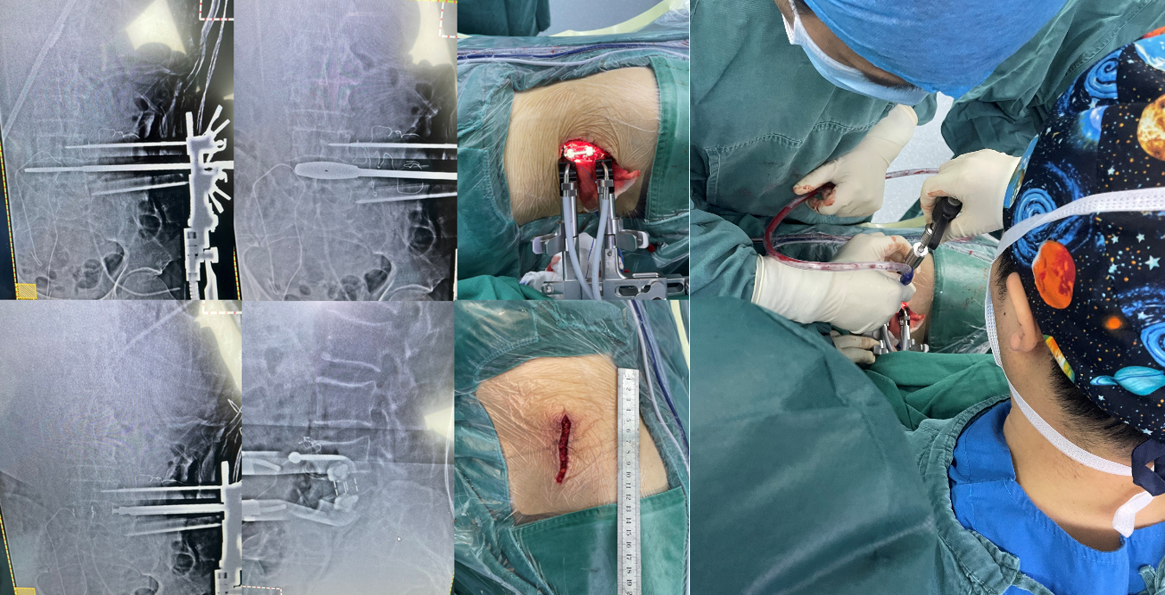

术中

第一例患者女性,73岁,因“腰部反复疼痛20余年,加重伴左下肢疼痛4月”以“腰椎滑脱症(L3、 I°)、腰椎管狭窄症”住院。入院后经术前讨论、评估后制定治疗方案,并与患者及其家属充分沟通,行OLIF手术。术后第二天,患者下地活动,腰痛和左下肢疼痛完全消失,无明显不适,疗效满意。

第二例患者男性,67岁,患者因“腰痛并右下肢放射痛1年余,加重1月”入院,发病以来反复保守治疗,未好转,1月前症状加重,间歇性跛行,行走100米后因疼痛无法继续行走。入院后经术前讨论、评估,制定治疗方案,行OLIF手术。次日患者下地活动,下肢症状消失,疗效满意。

第三例51岁女性患者,因“右下肢放射性疼痛、麻木1年,加重1月余”入院,发病以来反复多次保守治疗无效。入院后经术前讨论、评估,制定治疗方案,行OLIF手术,该病例采用后路经皮椎弓根螺钉内固定。次日患者下地活动,下肢症状消失,疗效满意。